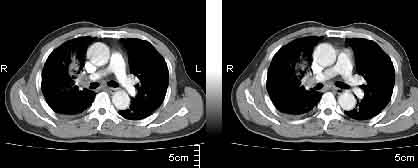

该病例我的诊断意见:右肺上叶周围型肺癌伴纵隔和右肺门淋巴结增大和右肺上叶阻塞性肺炎{病灶周围致密影以近肺门侧明显!}。右侧少量胸腔积液。

一. 1)症状有无发热及慢性过程.2)化验室检查?3)有无tb接触史?二.右肺上叶见片团状影,边界欠清,外侧方见一结节状软组织影,密度欠均匀,内可见低密度坏死区.周围强化明显,肺内见纤维索条影,局部胸膜增厚,但无明确胸膜凹陷.上叶支气管壁增厚,肺门及纵隔淋巴结增大.右侧胸腔少量积液.诊断意见:1右肺上叶慢性感染性疾病(肺tb?)伴肺门,纵隔淋巴结大.右胸少量积液.右肺上叶结节影多为tb球?2右肺上叶周围型肺ca伴肺门,纵隔淋巴结转移待排.右肺上叶炎变(肺门及纵隔淋巴结压迫).右胸少量积液.等待随返结果.

右上肺周围性肺癌,阻塞性肺炎考虑为肿大淋巴结压迫上叶支气管引起。